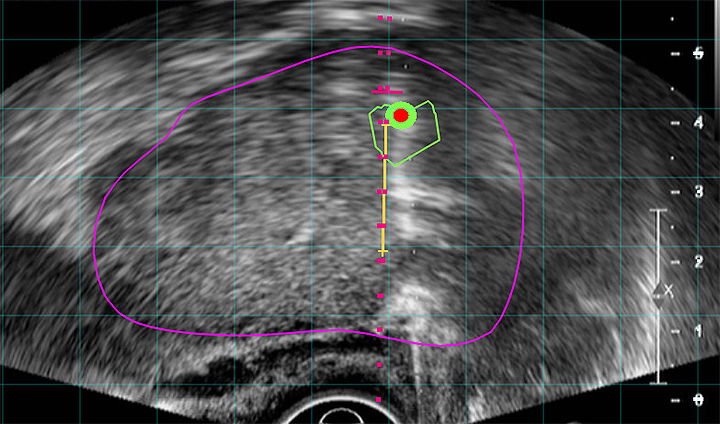

Targeted MR/Ultrasound Fusion Biopsy is becoming the new standard in prostate care. UroNav, a medical device by Philips, fuses pre-biopsy magnetic resonance (MR) images of the prostate with ultrasound-guided biopsy images in real time. This offers the best way to discern the prostate from suspicious lesions, providing the most powerful solution for analysis, planning, and targeted biopsy of the prostate. This approach consists of using DynaCAD software for Prostate and the UroNav fusion biopsy system–a comprehensive solution that offers cutting-edge imaging for patients with elevated and/or rising PSA levels.

The fusion of the MR and ultrasound images uses electromagnetic tracking, like your phone’s GPS system; a tiny tracking sensor attached to the trans-rectal ultrasound probe generates a small, localized electromagnetic field that helps isolate the location and orientation of the biopsy device. A sophisticated algorithm maintains the fusion of MR and ultrasound images, even if the patient moves.